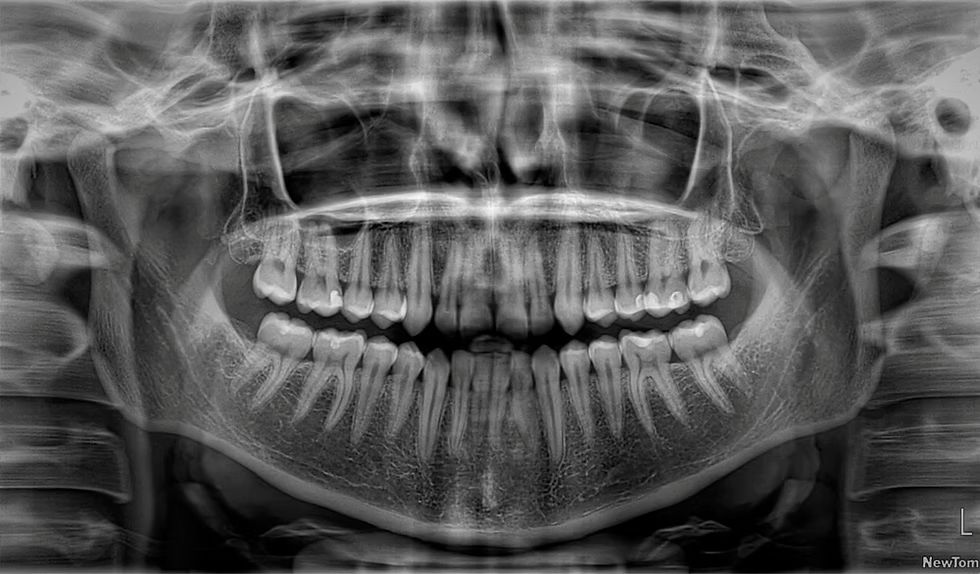

Radiografía panorámica digital

La radiografía panorámica es una prueba de imagen que muestra, en una sola toma, todas las estructuras de la boca, ofreciendo una visión global de la salud bucodental. Indispensable en varias especialidades dentales, como implantología, ortodoncia, cirugía, periodoncia y endodoncia.